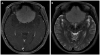

This article provides an overview of the neuroimaging literature focused on preoperative prediction of meningioma consistency. A validated, noninvasive neuroimaging method to predict tumor consistency can provide valuable information regarding neurosurgical planning and patient counseling. Most of the neuroimaging literature indicates conventional MRI using T2-weighted imaging may be helpful to predict meningioma consistency; however, further rigorous validation is necessary. Much less is known about advanced MRI techniques, such as diffusion MRI, MR elastography (MRE), and MR spectroscopy. Of these methods, MRE and diffusion tensor imaging appear particularly promising.